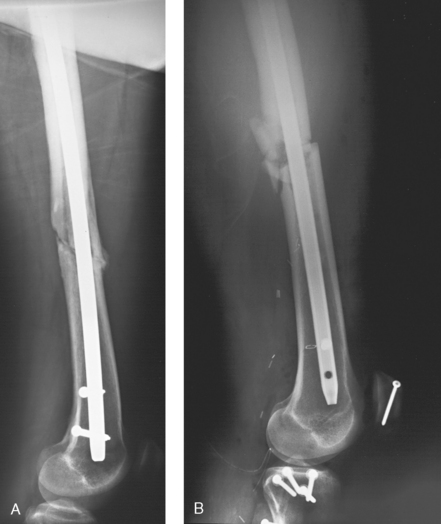

Structures shown: The distal two thirds of the femur, including the knee joint, are shown (Fig. 28-21).

Structures shown: This projection shows the distal two thirds of the femur, including the knee joint, without superimposition of the opposite thigh (Fig. 28-24).